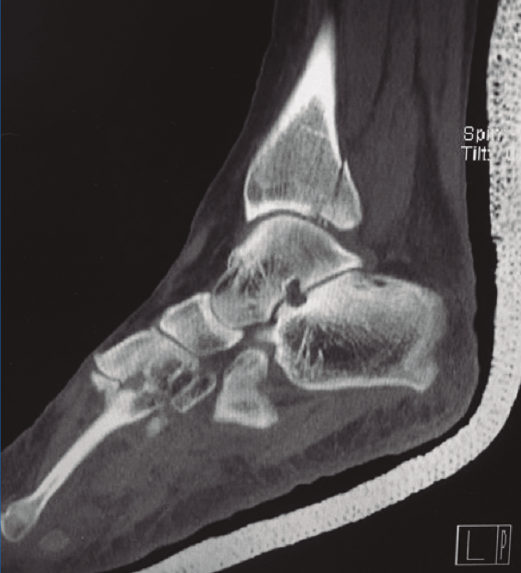

La exploración radiológica comprende las proyecciones AP, de la mortaja y lateral (L). En la proyección AP puede observarse el flake fragment sign o spur sign, que es un doble contorno del maléolo medial, indicativo de fractura del MP con extensión al maléolo interno. La TC es fundamental para reconocer la anatomía del fragmento, su propagación medial, conminución y número de fragmentos intermedios (Figura 1).

Figura 1. Tomografía computarizada que muestra fractura del maléolo posterior con pequeño fragmento intermedio.